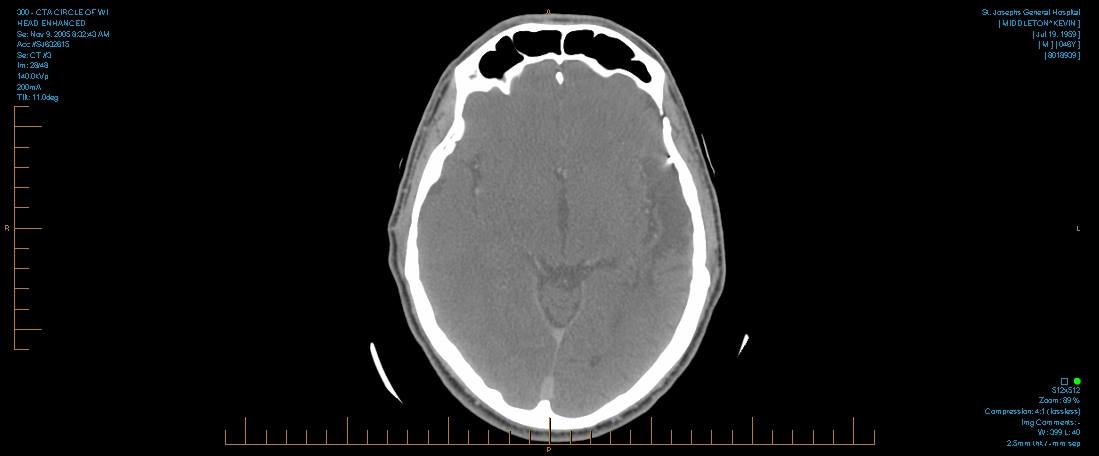

The paramedics took me to the Emergency Room of a nearby hospital where Donna made her first life-or-death decision – that I have immediate surgery instead of a CAT (computerized tomography) scan to see if the pressure from the brain-bleed had decreased. It’s clear now that the time that would been taken to do a CAT scan would have decreased my chance of survival by several hundred-fold.

After the first surgery, I was carefully transferred by ambulance to Columbia-Presbyterian Hospital in New York City. There, the neurosurgeon discovered an aneurysm that had to be removed. That was the second surgery. I survived … but the neurosurgeon had more bad news for Donna. She had to give permission for another dangerous surgery – to remove an AVM (arteriovenous malformation), a tangle of arteries and veins that can be a “time-bomb.” Miraculously, I survived that surgery too.